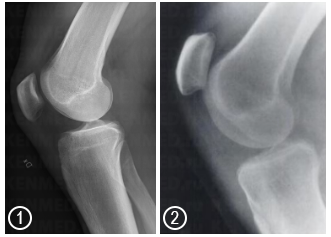

Расположение надколенника при нормальном функциональном состоянии (1) и при Patella Alta (2)